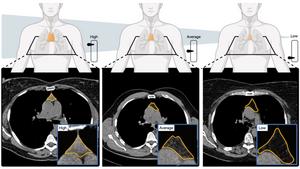

Mass General Brigham researchers developed a deep-learning, AI model that analyzes CT scans to estimate thymic health—an indicator of immune system function. This image depicts a comparison between high, average, and low thymic health, and corresponding CT images.

Credit: Mass General Brigham/Nature

The team analyzed the size, shape, and composition of the thymus, generating a “thymic health” score. People with high thymic health scores had about a 50% lower risk of death, 63% lower risk of cardiovascular death, and 36% lower risk of developing lung cancer compared to those with low thymic health. These associations remained significant after adjusting for age and other health factors.